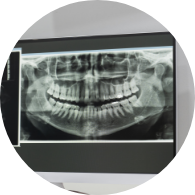

자료 채득

X-ray, 구강 내ㆍ외 카메라 사진, 치아 모형, 턱관절 및 치주 상태,

전신 질환 유무,

가족력 검사 등을 ​​​​​​​통해 진단 자료 수집